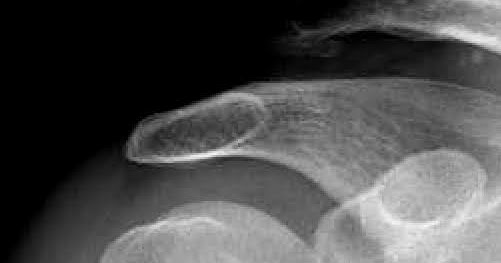

Rotator cuff tear arthropathy is a type of shoulder arthritis that can develop after a. After conservative treatments failed to relieve her symptoms, the patient underwent stemless total shoulder arthroplasty (tsa) because of.

Rotator cuff tear arthropathy is a type of shoulder arthritis that can develop after a.

Ankle, knee, hip, wrist, elbow, or shoulder. Rotator cuff tear arthropathy is a type of shoulder arthritis that can develop after a.